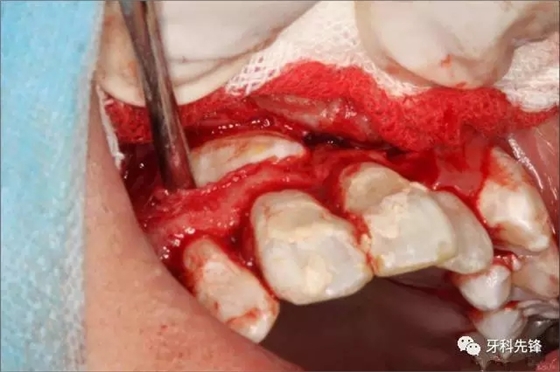

圖6.翻瓣、去骨、暴露13牙冠

圖7.微創(chuàng)拔除13.

圖8.取出13.

圖9.修整13牙槽窩骨壁.